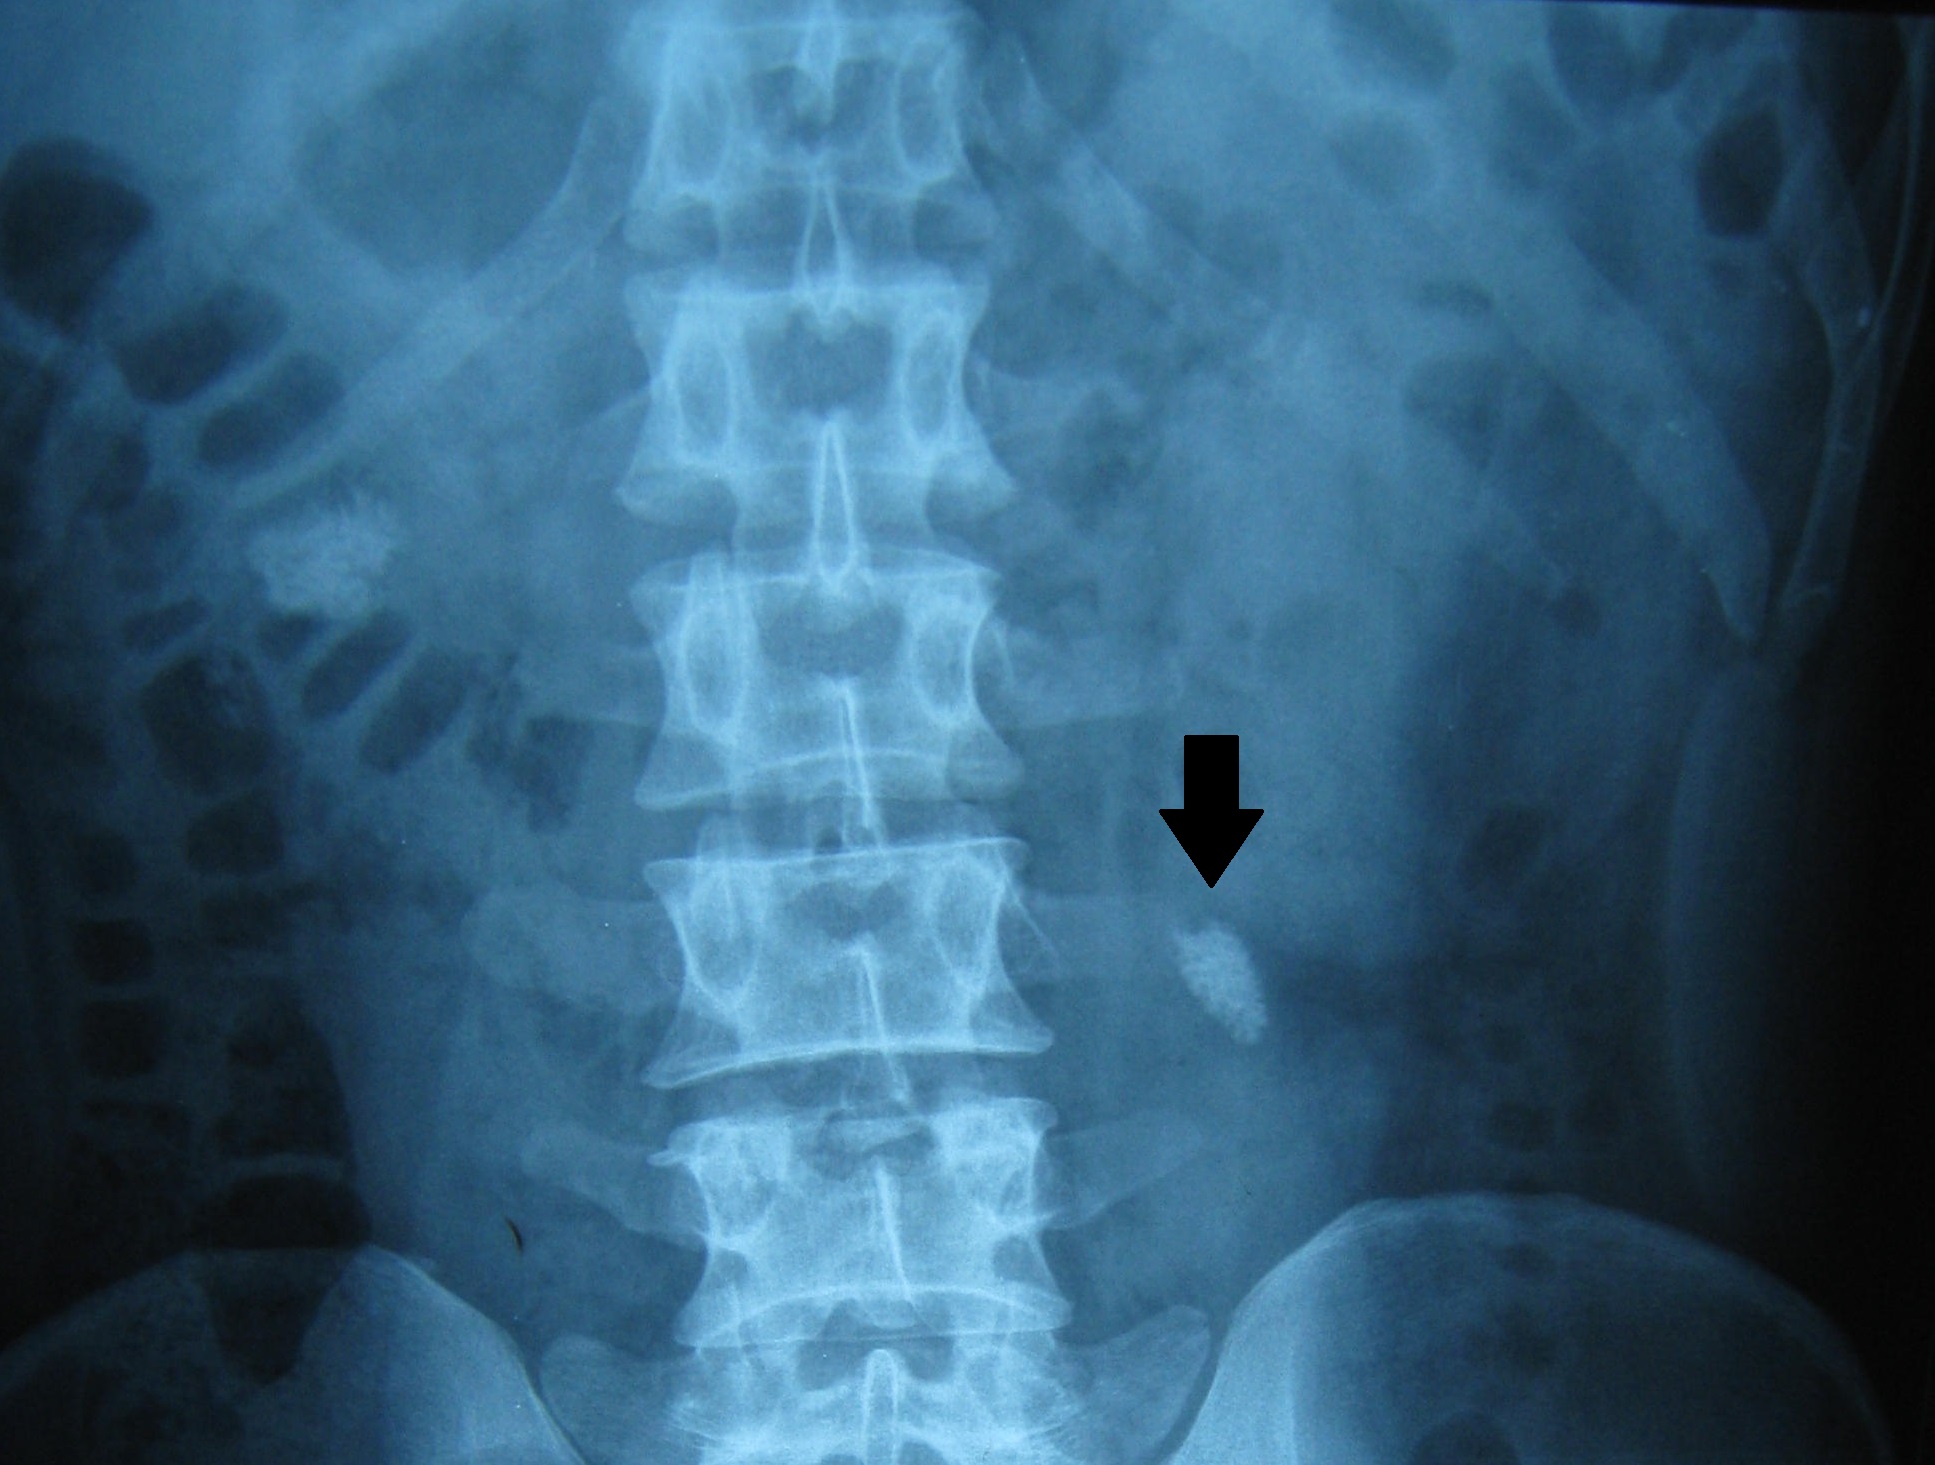

二、微创经皮肾镜取石术

微创经皮肾镜取石术是微创泌尿外科手术中的一个重要组成部分,在治疗上尿路结石方面,与输尿管镜取石术及体外冲击波碎石共同成为现代治疗尿路结石的主要方法,使得90%以上的上尿路结石病人不再需要开放手术。